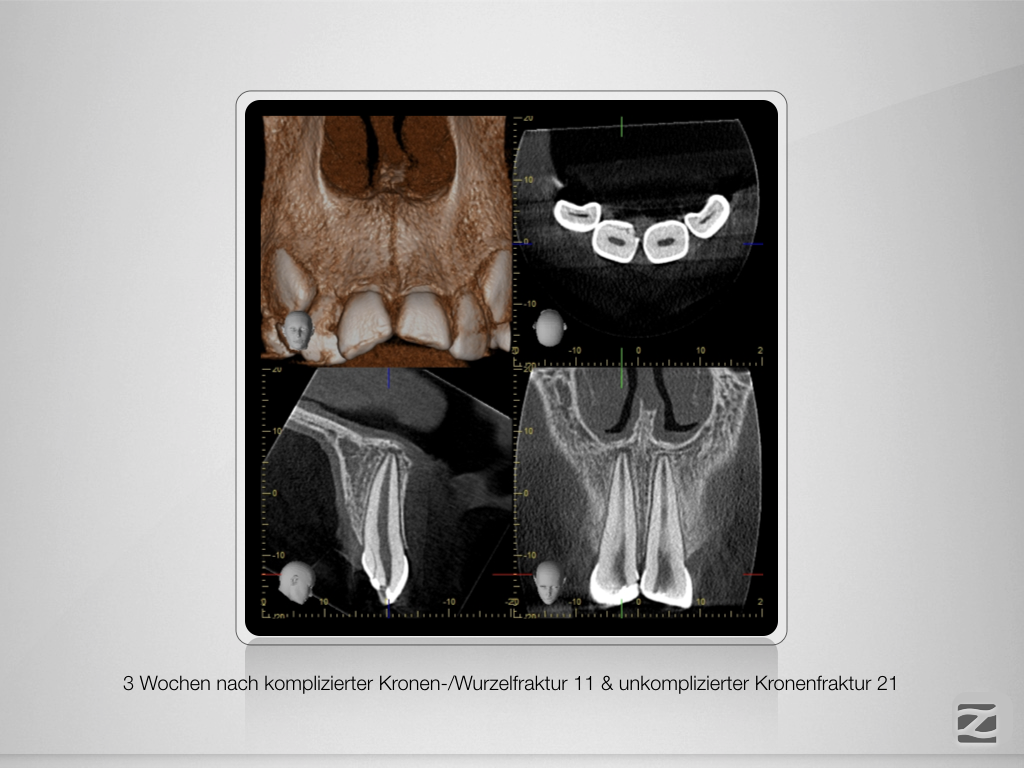

Frontzahntrauma – das klinische Vorgehen.